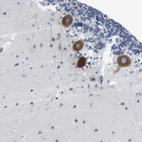

Immunohistochemical staining of human cerebellum shows strong cytoplasmic positivity in purkinje cells.